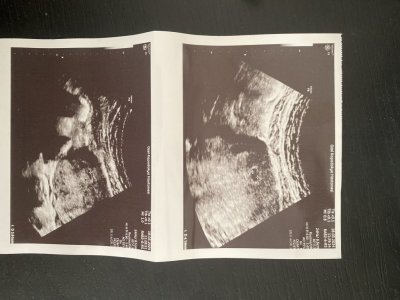

Doktor Ramzi isimli Kanada doktoru bebeğin cinsiyeti hakkında bir teori üretmiş. Plasentanın yerine bakarak cinsiyeti tahmin ediyormuş. %95 doğru çıkıyormuş. Meraklı anneler varsa sizinkine de eğlence amaçlı bakabilirim hem doğru mu görmüş oluruz. Teoriyi araştırıp ultrasondan kendiniz de bakabilirsiniz

Henüz 9. Haftadayim öğrenince unutmazsam söyleyeyim. Bende o teoriye bakarak kız diye düşündüm ama bilemiyorum bakalım gorcezRabbim tamamına erdirsin canımİşin uzmanı değilim ama plasenta solda galiba

Sen de bir bak kesenin hangi tarafı parlak duruyor canım? Ben kız diye tahmin ettim doğruysa öğrenmek isterim

Bende bebeğimin 8. haftada karından ultrason görüntüsünü atiyorum yorumları alayımDoktor Ramzi isimli Kanada doktoru bebeğin cinsiyeti hakkında bir teori üretmiş. Plasentanın yerine bakarak cinsiyeti tahmin ediyormuş. %95 doğru çıkıyormuş. Meraklı anneler varsa sizinkine de eğlence amaçlı bakabilirim hem doğru mu görmüş oluruz. Teoriyi araştırıp ultrasondan kendiniz de bakabilirsiniz

Canım benimki şu an sadece kese görünüyor ama cevaplarsan sevinirim, merak ediyorum daDoktor Ramzi isimli Kanada doktoru bebeğin cinsiyeti hakkında bir teori üretmiş. Plasentanın yerine bakarak cinsiyeti tahmin ediyormuş. %95 doğru çıkıyormuş. Meraklı anneler varsa sizinkine de eğlence amaçlı bakabilirim hem doğru mu görmüş oluruz. Teoriyi araştırıp ultrasondan kendiniz de bakabilirsiniz

ya parlaklık tam aşağıda duruyor ben de uzman değilim kiBende bebeğimin 8. haftada karından ultrason görüntüsünü atiyorum yorumları alayım

çok küçükk 6-9 hafta arası tahmin ediliyorCanım benimki şu an sadece kese görünüyor ama cevaplarsan sevinirim, merak ediyorum da

Canım bugün 6 haftalığa girdim doktor ultrason kağıdı verdi ama kesenin etrafında kanamalar var dedi, Bir de çocuğun kalbi atmıyor şu ançok küçükk 6-9 hafta arası tahmin ediliyorrabbim sağlıkla kucağına almayı nasip etsin

Hayırlısı olsun rabbim hayırlı ve sağlıklı evlatlar nasip etsin inşallahCanım bugün 6 haftalığa girdim doktor ultrason kağıdı verdi ama kesenin etrafında kanamalar var dedi, Bir de çocuğun kalbi atmıyor şu an